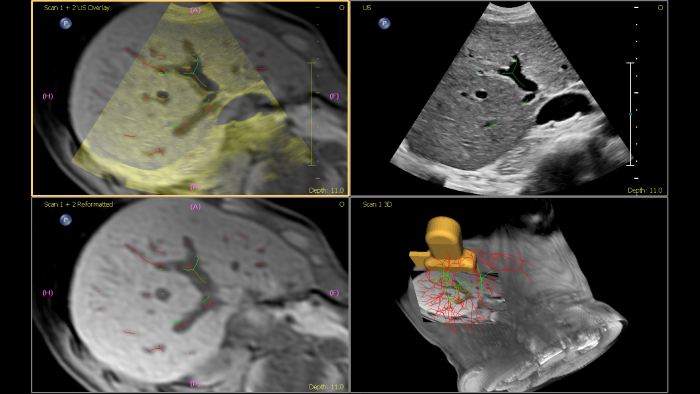

Philips ultrasound systems for interventional radiology support a range of sophisticated capabilities for interventional applications. Streamlined workflow allows clinicians to achieve fast and effective fusion of CT/MR/PET/CBCT with live ultrasound, while needle navigation aids in guiding biopsy and ablation of small and difficult-to-access lesions. Fusion and navigation can also be used in conjunction with Contrast-Enhanced Ultrasound (CEUS), giving clinicians access to even more powerful diagnostic tools with advanced visualization.

This semi-automated tool helps outline a 3D contour around a structure of interest, improving procedure guidance even in challenging cases where the lesion may not be visually obvious under ultrasound. The lesion can be rendered in 3D or 2D via a complementary modality and overlaid on the live ultrasound or CT, helping visualize the location in relation to surrounding critical structures.